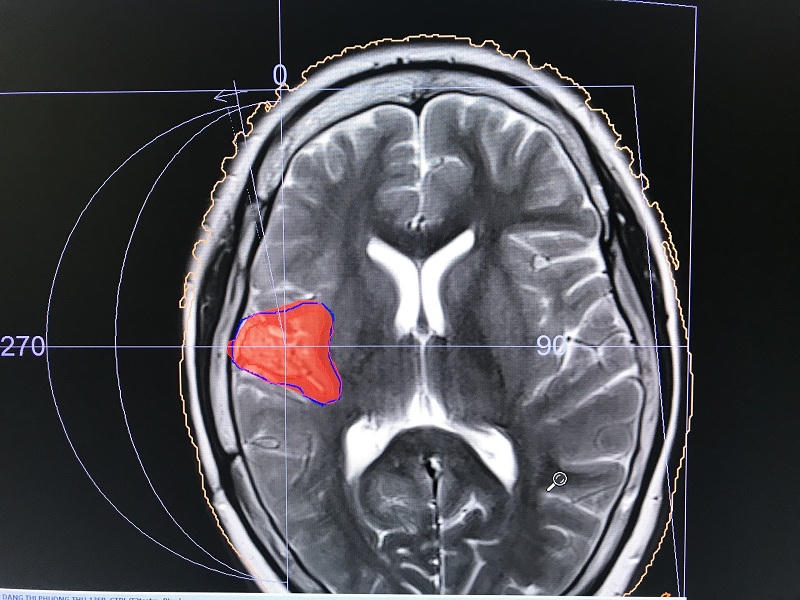

Kết quả chụp cộng hưởng từ não cho thấy có tổn thương tồn dư vùng hồi nắp và thùy đảo bán cầu phải, phù hợp cơn động kinh trên lâm sàng và các bất thường trên điện não đồ sau phẫu thuật.

Dưới sự chủ trì hội chẩn đa chuyên khoa trực tuyến của GS.TS Phạm Như Hiệp – Giám đốc Bệnh viện Trung ương Huế, các chuyên gia về phẫu thuật thần kinh, nội thần kinh, nhi thần kinh, chẩn đoán hình ảnh, bác sĩ xạ trị/xạ phẫu của bệnh viện đã thảo luận nhiều lần về các phương án tối ưu nhất để điều trị cho bệnh nhi. Sau thời gian hội chẩn, các y bác sĩ thống nhất lựa chọn phương án xạ phẫu vào ổ tổn thương tồn dư vùng hồi nắp và thùy đảo bán cầu phải sau phẫu thuật theo khuyến cáo của các chuyên gia về động kinh ở trong nước và nước ngoài.

Ngày 29/1, TS.BS Phan Cảnh Duy - Phó Khoa Xạ trị, Trung tâm Ung bướu Bệnh viện Trung ương Huế, người trực tiếp thực hiện kỹ thuật này - cho biết: bệnh nhân đã được xạ phẫu thành công, chính xác vào tổn thương tồn dư gây động kinh, vùng não lành kế cận không bị ảnh hưởng. Ngay sau khi xạ phẫu bệnh nhi hoàn toàn tỉnh táo, giao tiếp bình thường, chưa thấy cơn động kinh tái phát hoặc tăng lên. Bệnh nhân sẽ được tiếp tục dùng thuốc, theo dõi thêm một vài ngày trước khi xuất viện và cần theo dõi thêm 3 đến 6 tháng để đánh giá chính xác hiệu quả về kiểm soát động kinh bằng xạ phẫu.